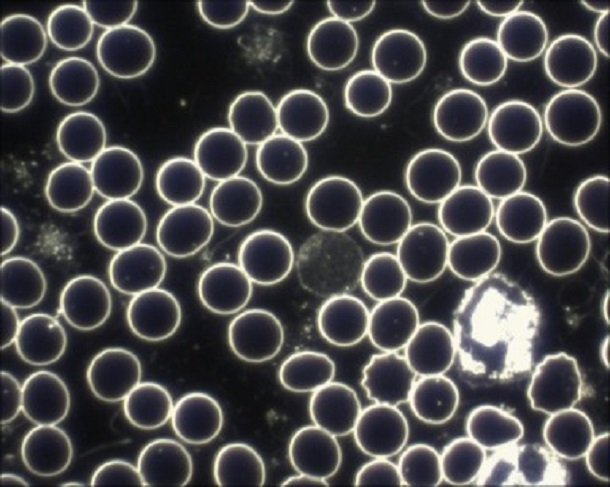

Hier ein Beispiel:

Beim Betrachten der beiden Aufnahmen sehen Sie den grundsätzlichen Unterschied. Um beim Beispiel „Himmel“ zu bleiben: Selbst wenn der Himmel wolkenlos ist, sieht man mit dem bloßen Auge nur die Sonne, vielleicht noch den Mond. Die umliegenden Sterne bleiben dem Auge verborgen – eine Metapher, die das grundsätzliche Prinzip der Dunkelfeldmikrokopie auch für Laien sehr anschaulich erklärt.

Das Besondere bei der Dunkelfeld-Diagnostik: Es gelangt nur das Licht ins Mikroskopbild, welches seitlich an den im Blut befindlichen Strukturen vorbei scheint. Somit heben sich alle Präparate im Blut durch das Mikroskopbild ab.

Man sieht also alles, was im Blut vorhanden ist, ohne dem Körper vorher etwas zufügen zu müssen, um diese sichtbar zu machen. Daher lassen sich auch lebende Organismen und Lebewesen schonend und sehr gut durch das Dunkelfeldmikroskop erkennen. Heute wird die Dunkelfeldmikroskopie nicht nur bevorzugt in der Biologie, beispielsweise bei der Beobachtung von mit dem bloßen Auge nicht sichtbaren Wasserlebewesen, verwendet, sondern immer öfter auch in der Medizin.

Für das Verfahren werden keine Kontrastmittel oder Fixierer benötigt, um mögliche Krankheitserreger oder andere Schadstoffe im Blut sichtbar zu machen – und genau hier liegt einer der größten Vorteile der Dunkelfeldmikroskopie. Da dem Blut vor der Betrachtung nichts zugeführt werden muss, nennt man dieses Verfahren auch Vitalblut-Untersuchung: man sieht das „lebende“ Blut und dessen Bestandteile.